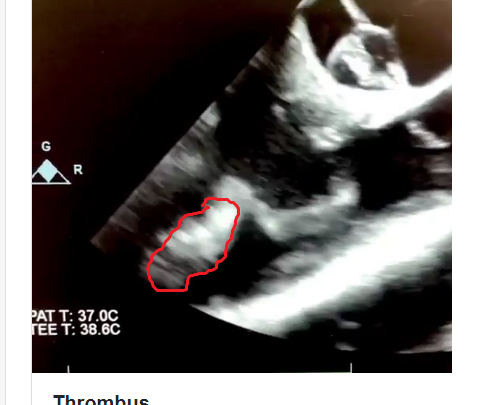

Lead extraction and goobers case.

Not sure if clips are uploading. Hopefully they are.

Comments, concern, plan?

As far as thrombus burden, granted we only have one view to look at but we do need to consider that that thing is totally enveloping multiple centimeters of the distal part of that lead. I'm thinking about it like a vine wrapping up a telephone pole. The vine has a pretty slim profile as is but imagine how much plant mass you have if you stripped it off the pole and bunched it up.

Not to mention it looks like there's a good bit of secondary non-mobile thrombus that may be distinct from the mobile schmutz on the lead that's catching everyone's eye (see below between the red arrows).

As per this particular patient, the thrombus is a monster and was literally ebb and flowing in and out of the pulmonary valve. There is no doubt in my mind that if this thing were to embolize, it would cause harm. Not only is it large, but certain aspects of it are very well organized and would not be easy to tpa if it ended up in the lungs. That being said, the patient was 30 years old and had no other heart issues (good EF, etc).

Ultimately, cardioligy struggled getting this thing out (had 20 years to bury itself into a developing heart). Cards became very reluctant to pursue the lead once i showed him what we were dealing with. This particular cardiologist starts to think of surgical intervention once it is 3-4cm in size. TEE demonstrated at least a 7 cm mass which was likely even bigger. Cards persisted in trying to get it out until his lead extender/sheath broke off at which point the solution became obvious. Pump run for lead extraction which in all honesty would have been a good choice from the get-go as we had an otherwise healthy patient/good protoplasm. Downside would be the scar in a young patient. TPA or anticoagulants were not going to dissolve the proximal thrombus and in the meantime he was at risk for a major card/pulm risk.